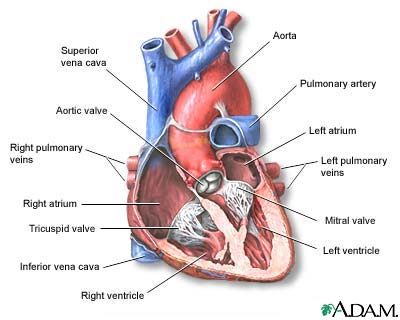

- Before birth, the baby has a blood vessel that runs between the aorta (the main artery to the body) and the pulmonary artery (the main artery to the lungs), called the ductus arteriosus. This small vessel most often closes shortly after birth when the baby starts to breathe on their own. If it does not close. It is called a patent ductus arteriosus. This could cause problems later in life.

- The atrial septum is the wall between the left and right atria (upper chambers) of the heart. A hole in that wall is called an ASD. In the presence of this defect, blood with and without oxygen can be mixed up over time, causing medical problems and arrhythmias.

- The ventricular septum is the wall between the left and right ventricles (lower chambers) of the heart. A hole in the ventricular septum is called a VSD. This hole lets blood with oxygen mix with used blood (that has a low oxygen level)

- In a normal heart, the aorta comes from the left side of the heart, and the pulmonary artery comes from the right side. In children with transposition of the great vessels, these arteries come from the opposite sides of the heart. The child may also have other birth defects.

- The tricuspid valve is between the upper and lower chambers on the right side of the heart. Tricuspid atresia occurs when this valve is deformed, narrow, or missing.